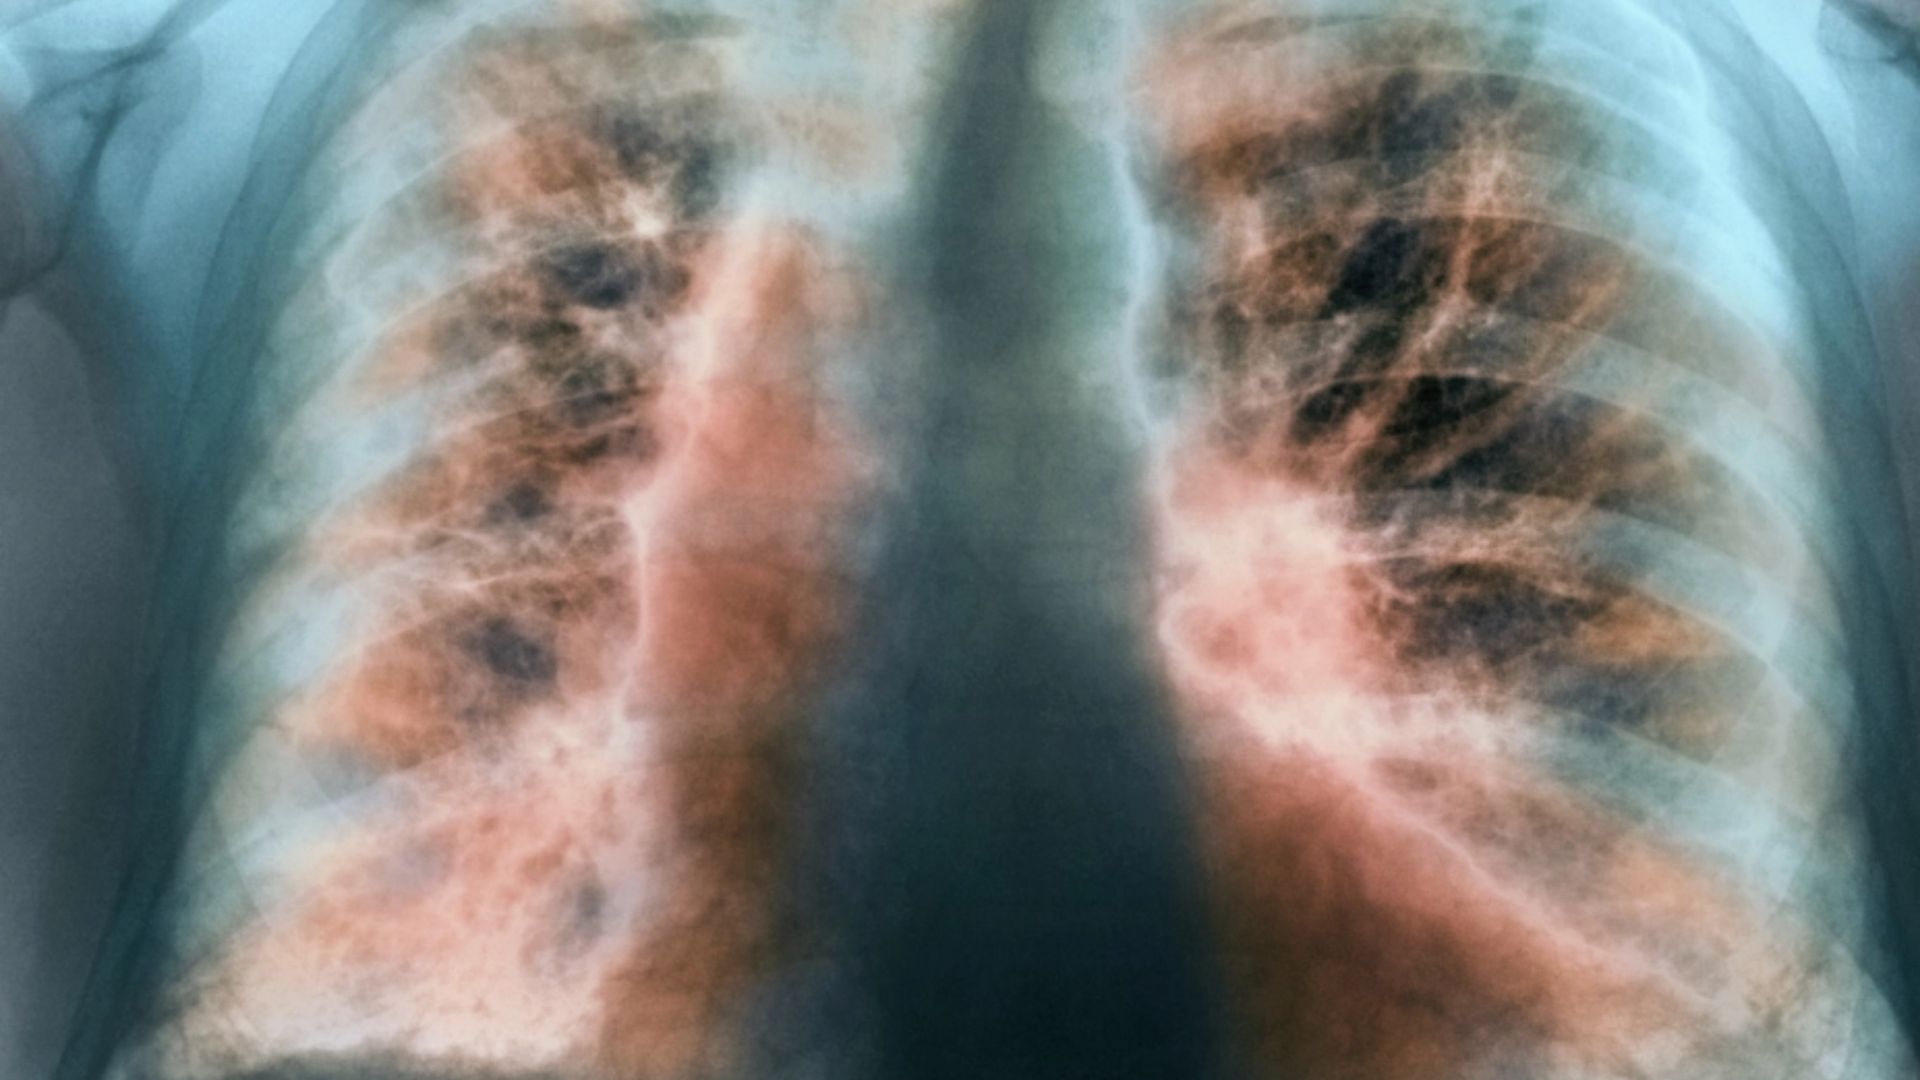

ফুসফুসের ক্যানসারের কারণ ও লক্ষণ, প্রতিরোধে যা করবেন

ডা. আব্দুস শাকুর খান বলেন, ফুসফুসের ক্যানসার হচ্ছে ফুসফুসের এক ধরনের টিউমার। অর্থাৎ ফুসফুসের যে স্বাভাবিক কোষ আছে সেই স্বাভাবিক কোষের যখন অস্বাভাবিক এবং অনিয়ন্ত্রিত বৃদ্ধি হয়ে চাকার মত সৃষ্টি করে, তাকেই ফুসফুস ক্যানসার বলে। এটি শরীরের জন্য মারাত্মক ক্ষতিকর। ক্যানসার যখন ফুসফুসে হয় এটা শুধু নির্দিষ্ট জায়গায় থাকে না বরং অস্বাভাবিক এবং অনিয়ন্ত্রিত বৃদ্ধির কারণে শরীরের অন্যান্য অংশেও ছড়িয়ে পড়ে। সঠিক সময়ে শনাক্ত ও যথাযথ চিকিৎসার অভাবে শেষ পর্যন্ত মৃত্যুরও কারণ হয়ে থাকে।